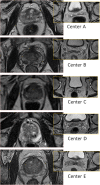

Background: The use of magnetic resonance (MR) imaging as a part of preparation for radiotherapy is increasing. For delineation of the prostate several publications have shown decreased delineation variability using MR compared to computed tomography (CT). The purpose of the present work was to investigate the intra- and inter-physician delineation variability for prostate and seminal vesicles, and to investigate the influence of different MR sequence settings used clinically at the five centers participating in the study.

Methods: MR series from five centers, each providing five patients, were used. Two physicians from each center delineated the prostate and the seminal vesicles on each of the 25 image sets. The variability between the delineations was analyzed with respect to overall, intra- and inter-physician variability, and dependence between variability and origin of the MR images, i.e. the MR sequence used to acquire the data.

Results: The intra-physician variability in different directions was between 1.3 - 1.9 mm and 3 - 4 mm for the prostate and seminal vesicles respectively (1 std). The inter-physician variability for different directions were between 0.7 - 1.7 mm and approximately equal for the prostate and seminal vesicles. Large differences in variability were observed for individual patients, and also for individual imaging sequences used at the different centers. There was however no indication of decreased variability with higher field strength.

Conclusion: The overall delineation variability is larger for the seminal vesicles compared to the prostate, due to a larger intra-physician variability. The imaging sequence appears to have a large influence on the variability, even for different variants of the T2-weighted spin-echo based sequences, which were used by all centers in the study.